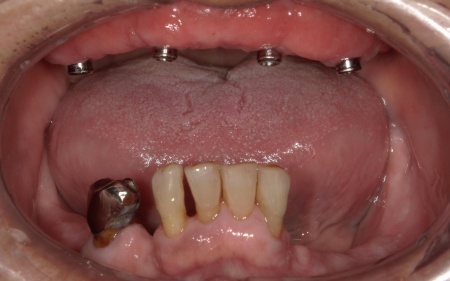

当初は、上顎に残存歯(残根)を残したまま装着する「残根上義歯(オーバーデンチャー)」にて治療することを提案し、治療を進めていました。

そのため、顎の骨に埋め込んだ人工歯根を支えとして、取り外し可能な義歯を装着する「インプラント義歯」へ変更することを再提案し、同意いただいています。

まず、上顎の状態や残存歯について詳しく検査し、温存が難しいと判断した左上の歯3本(犬歯、第1小臼歯、第2小臼歯)を抜きました。

抜歯後は、即時インプラント埋入手術を実施しています。

インプラント埋入後は経過観察を行い、歯茎と顎の骨が治癒するのを待ちます。

傷が治り、インプラントが顎の骨にしっかりと結合したことを確認したら、インプラントの頭部分に入れ歯と連結するための部分となる「アタッチメント」を装着しました。